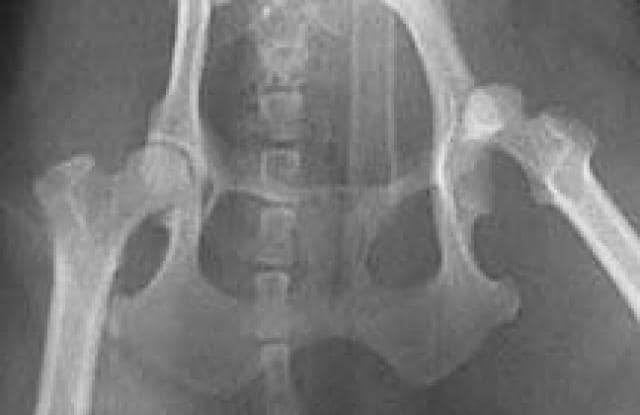

In contrast a dislocated toe happens due to the complete tear of a collateral ligament. Dog Hip Dislocation is a disease that can attack older animals or younger ones alike. Boxers and spaniel breed dogs may be more prone to fracture of the radial carpal bone. Instead of luxation where the joint has fully dislocated it is possible for dogs to be afflicted with subluxation in which the joint does not sit well within the socket. A dislocated hip occurs when the ball part of the joint the end of the leg bone comes out of the socket the pelvis oftentimes caused by blunt trauma.

They may experience pain depending upon the extent of damage. The dog may need surgery. Hip dislocation in dogs occurs when the femoral head loses its close association with the acetabulum. Dislocated kneecaps are usually due to a congenital defect but can also be the result of trauma. He doesnt seem to be in too much pain.